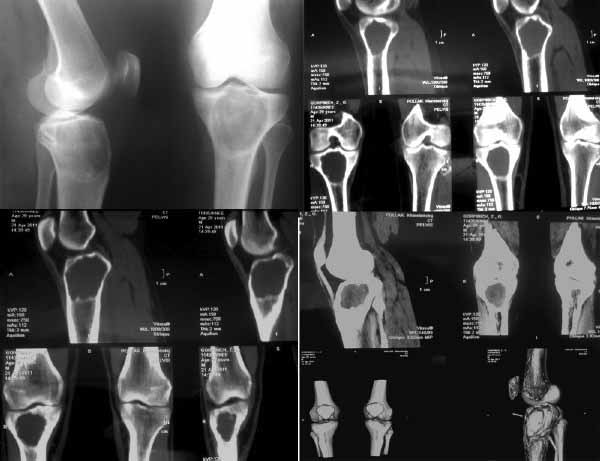

К нам обратилась пациентка 29 лет.  В конце марта после нагрузки появился дискомфорт в коленном суставе. К коллегам обратилась в апреле, при рентгенографии обнаружена солитарная костная киста? (фиброзная дисплазия?)

Рентгенограммы и СКТ прилагаются.

Планируется экскохлеация, костная ауто-аллопластика кортикально-губчатыми гранулами.

Интересует ваше мнение об иммобилизации конечности после данного этапа: внешняя иммобилизация, наружный или погружной фиксатор (есть возможность использования LCP. В таком случае больше подойдёт медиальная/латеральная мыщелковая пластина?)